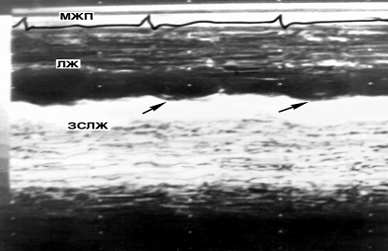

Рис. 10. Эхокардиограмма больного с постинфарктным кардиосклерозом (эхопозитивное пространство отображено светлыми полями): видна зона дискинезии задней стенки левого желудочка в виде противонаправленного движения (указано стрелками) в систолу